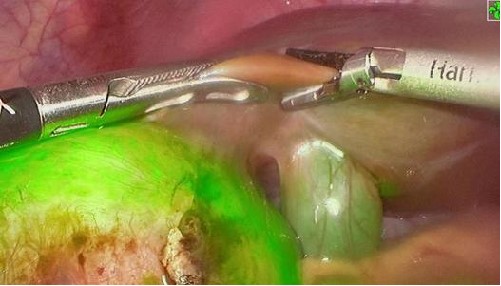

PL002是浙江普利药业有限公司研发的荧光/磁共振双模态造影剂,荧光/磁共振双模态造影剂的成功研发将成为提高脑胶质瘤手术效率的有效方案。术中荧光技术与核磁共振成像的结合,相较于单独使用,能够更准确地识别肿瘤组织与功能区的位置关系,以及患者的肿瘤浸润边缘。这种联合使用不仅能在保留患者功能的前提下实现功能区脑胶质瘤的最大限度安全切除,还能有效降低术中神经损伤的风险。